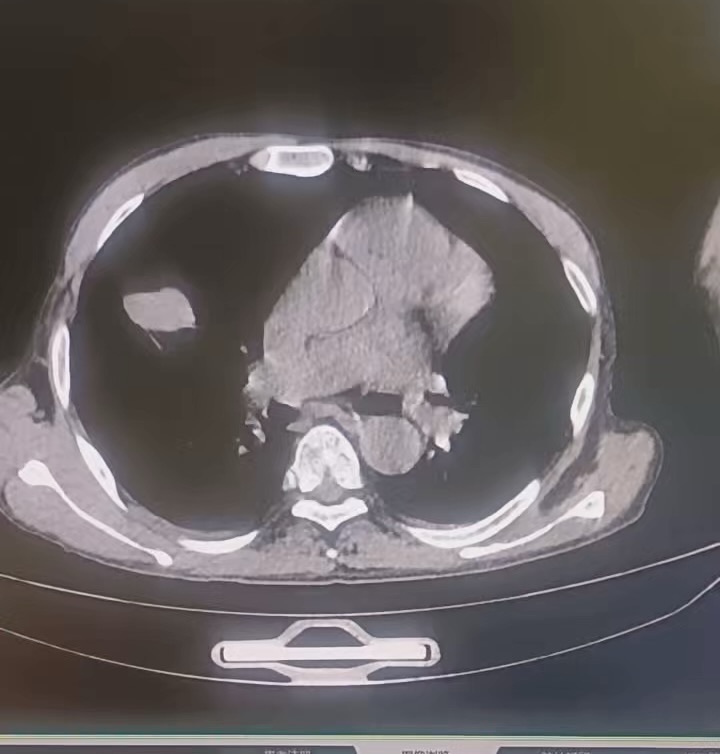

【患者信息】:男,55岁

【主诉】:腰疼。